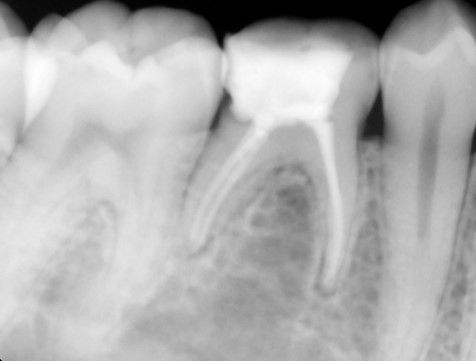

- Unhealthy pulp is removed. The length of the root canal is determined with the help of Electronic Apex locators as well as radiographs. The canals are then cleaned, enlarged and shaped with special caliberated instruments and disinfecting solutions.

- Periodic Radiographs (X rays) using digital RVG are taken during the treatment.

- Once the tooth is free of infection, the tooth is filled with a special root canal filling material like gutta percha and the access previously opened is sealed permanently with a Core filling.